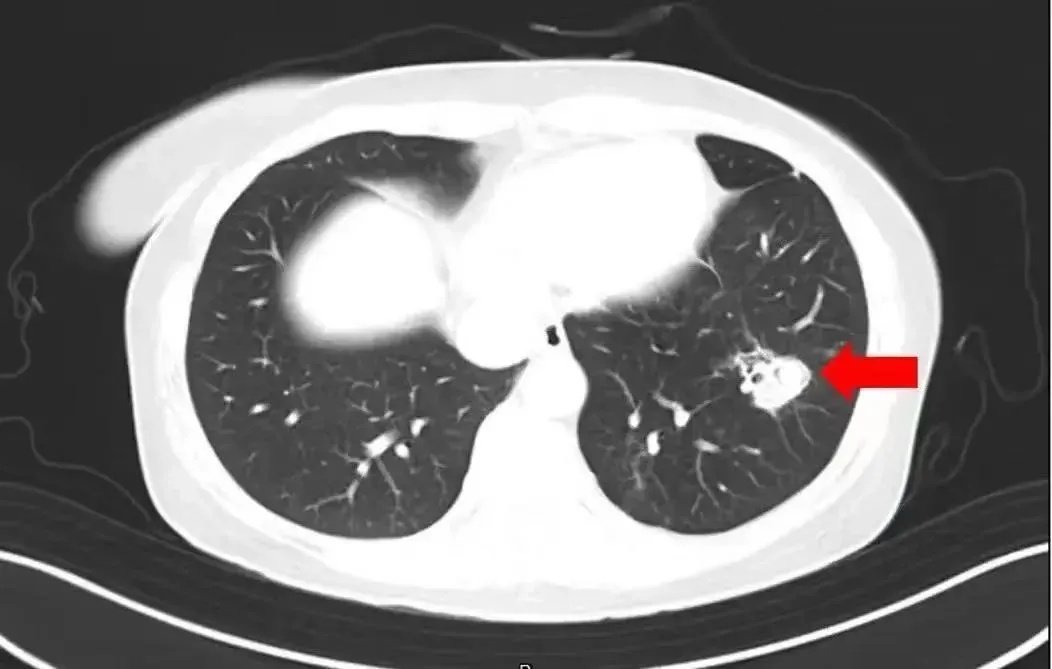

为进一步确诊病情,医生为她进行纤维支气管镜检查及肺泡灌洗液病原体检测,果然发现气道壁上有大量白色菌斑,化验后确认是曲霉菌。

图源:健康杭州